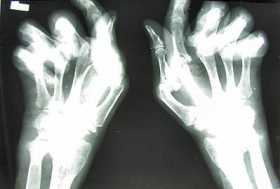

La artritis también afecta a los jóvenes